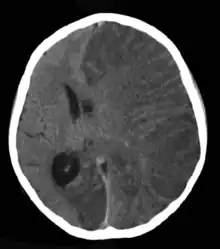

| Brain CT scan without contrast enhancement of a patient, female, 8 years old, with Rasmussen's encephalitis. |